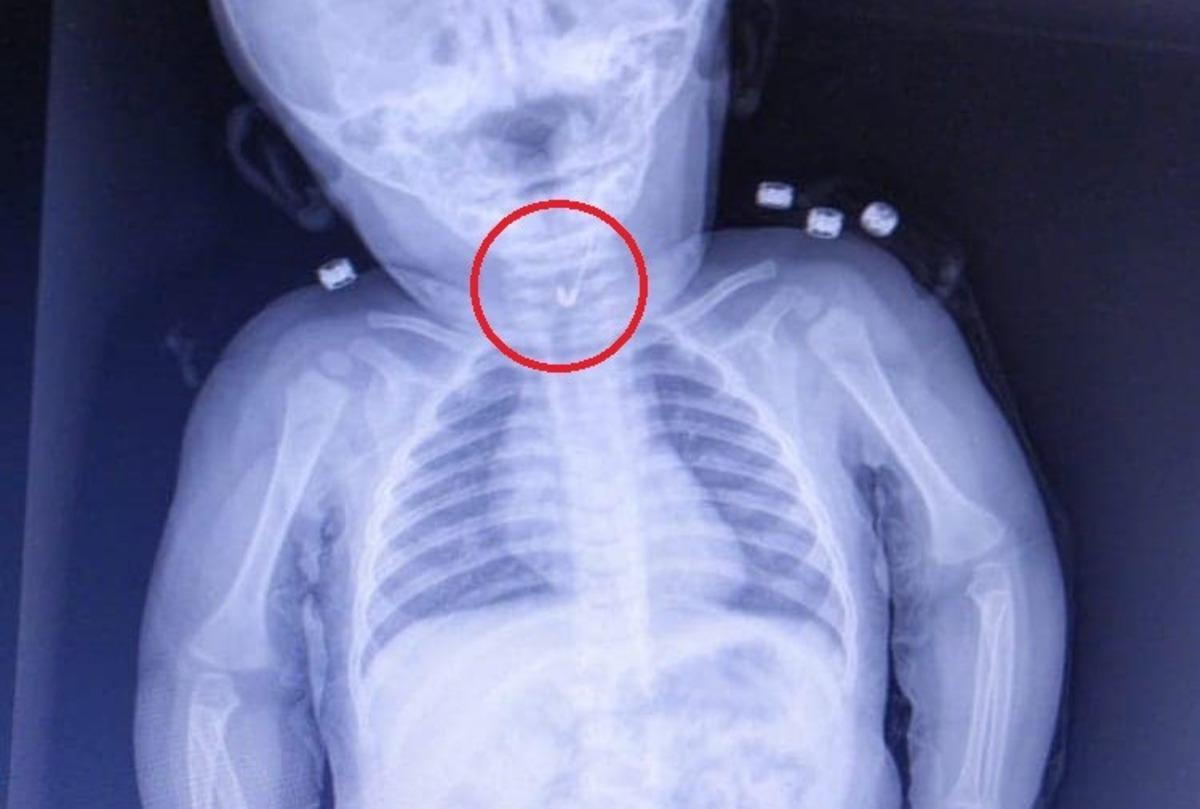

Tekirdağ'da yemek borusuna çengelli iğne kaçan 7 aylık bebek, hastanede yapılan operasyonla kurtarıldı. Ucu açık iğne yemek borusuna takılan bebeğin sağlığının iyi olduğu öğrenildi.

Tekirdağ’da 7 aylık bir bebek, yemek borusuna çengelli iğine kaçması sonucu Tekirdağ Devlet Hastanesine sevk edildi. 7 aylık erkek bebeğin yutup yemek borusuna takılan açık çengelli iğne Tekirdağ Devlet Hastanesi’nde yapılan girişim ile başarıyla alındı. Gastroenterolojik Cerrahi Uzmanı Dr. İhsan Gündüz ile Anestezi Uzmanı Dr. İbrahim Çetin’in yaptığı operasyon sonucu bebek sağlığına kavuştu.